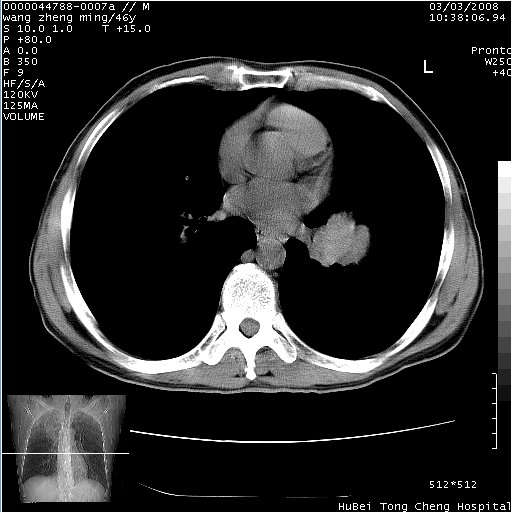

以下是引用卜一在2008-3-22 1:37:00的发言:[br]右肺实质性肿块,边缘不整,明显见毛刺征 分叶征及胸膜凹陷征,右上叶支气管明显变窄,远端散在的片状 斑片状实变影。另:左肺门较大肿块,支气管受累 变窄,远侧见阻塞性肺炎。纵隔内见肿大淋巴结。多考虑:右肺周围性肺癌伴左肺门 纵隔淋巴结转移!